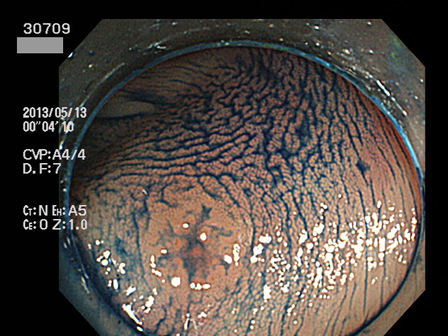

上記100名より抽出した平坦・陥凹型腺腫(=癌化の危険が高いが見落としやすい病変)の内視鏡写真